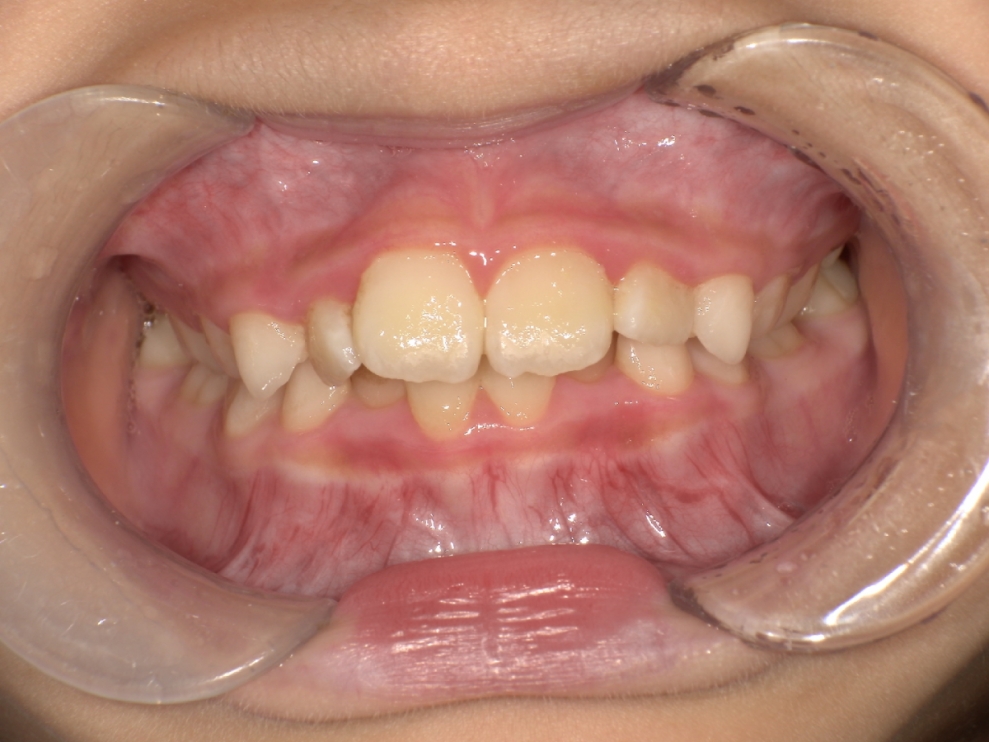

BEFORE

スタート時8歳の女の子の症例です。主訴は歯並びのガタつきでした。2年前に歯科医院で「顎が小さく、このままだと歯並びが悪くなる可能性がある」と指摘を受けていたことや、学校健診でチェックが入ったことをきっかけにご相談に来院されました。診査の結果、歯列のガタつきに加え、深い噛み合わせの状態も確認されました。

できるだけ痛みや不快感の少ない方法で治療を進めたいとのご希望があり、「しっかり治るのであれば期間にはこだわらない」と前向きなお気持ちで治療に臨まれました。